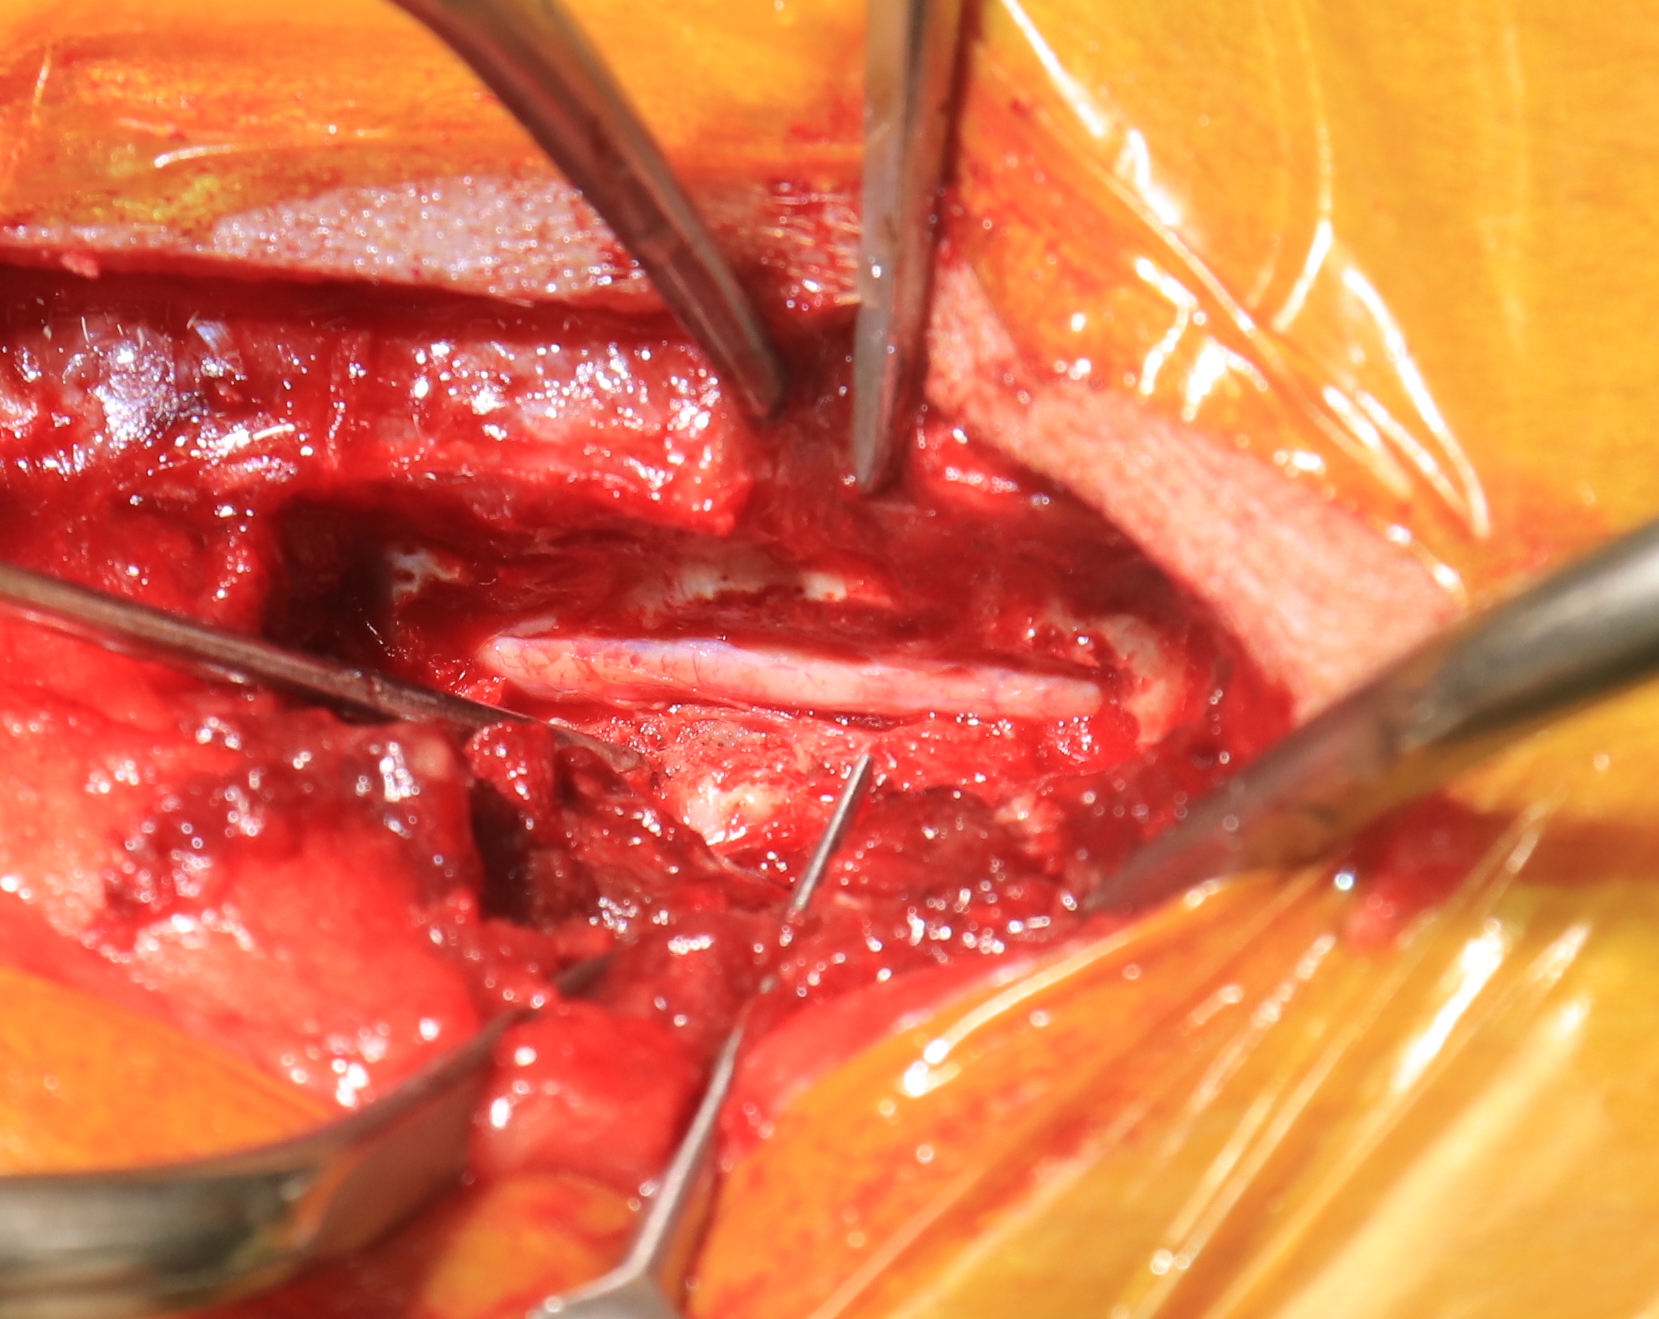

8才7ヶ月齢ミニチュアダックスフンド グレード5のT12-13椎間板ヘルニアです。病変部からT8までの脊髄はT2強調で高信号を呈しており、画像上、脊髄軟化症が強く疑われました。即日手術となり片側椎弓切除を実施したところ、硬膜には発赤が認められました。硬膜切開を実施したところ脊髄は軟化しており、後に病理組織検査で脊髄軟化症と診断されました

従来、脊髄軟化症は進行性であり、3-10日ほどの経過で100%死亡するとされていますが、近年、拡大的な減圧術を行うことにより救命可能となった症例が少しずつ蓄積されております。本症例においても拡大的椎弓切除+硬膜切開を行いました。T7よりも頭側の脊髄は肉眼的に正常な脊髄でした